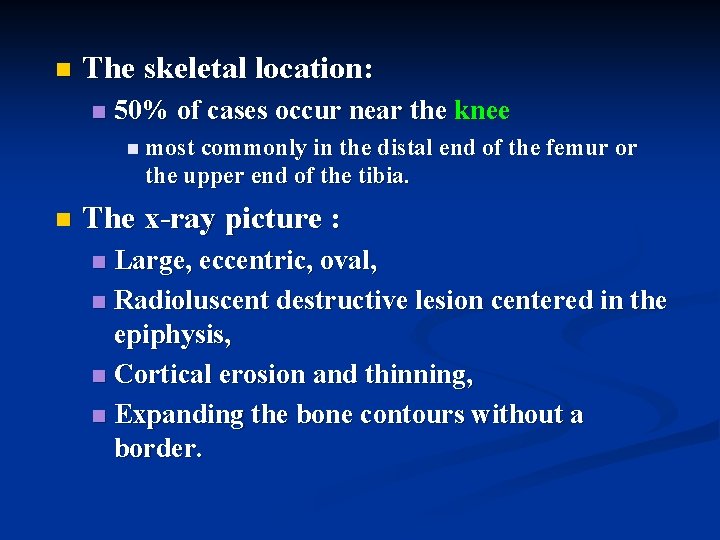

Giant Cell Tumor An aggressive benign tumor n Composed of : n well vascularized stroma n plump, spindly, and oval tumor cells n multinucleated tumor giant cells n n Over the age of 20: most commonly in the third decade of life n slight female preponderance n

n The skeletal location: n 50% of cases occur near the knee n most commonly in the distal end of the femur or the upper end of the tibia. n The x-ray picture : Large, eccentric, oval, n Radioluscent destructive lesion centered in the epiphysis, n Cortical erosion and thinning, n Expanding the bone contours without a border. n